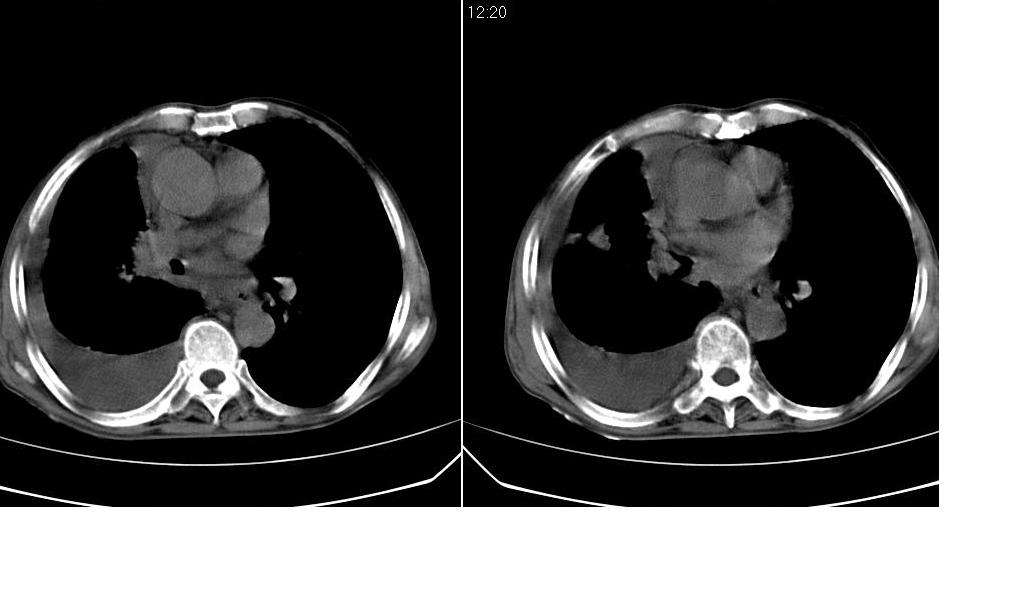

以下是引用zsl6918在2008-5-3 19:53:00的发言:[br]右肺中心型肺癌并纵隔淋巴结转移,胸膜转移,右肺癌性淋巴管炎。

以下是引用liuyue在2008-5-3 20:49:00的发言:[br]1.右侧中心型肺癌伴双肺转移瘤、纵隔淋巴结转移、右侧胸腔积液(侵及胸膜所致可能性大)。[br]2.右肺阻塞性肺炎,癌性淋巴管炎不除外。

以下是引用mzh123在2008-5-3 21:12:00的发言:[br]本人持有不同观点[br]1、右肺似有团块表现,但只有一个层面,所以本人认为还是以片为主,所以不能首先考虑肿瘤[br]2、右肺普遍成纤维化改变 并伴有片状炎症改变,和癌性淋巴管炎表现不同[br]3、所以本人认为是间质纤维化伴感染可能大 及胸腔积液